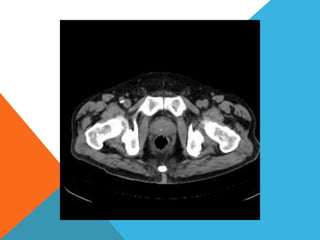

El paciente presentó síntomas de sangrado digestivo y pérdida de peso. Exámenes revelaron gastritis crónica asociada a H. pylori. Un tumor fue descubierto en una colonoscopia normal. La cirugía removió un tumor fibroide solitario, una rara neoplasia mesenquimal que usualmente crece lento y tiene bajo potencial de malignidad. El pronóstico después de la remoción quirúrgica es generalmente bueno.